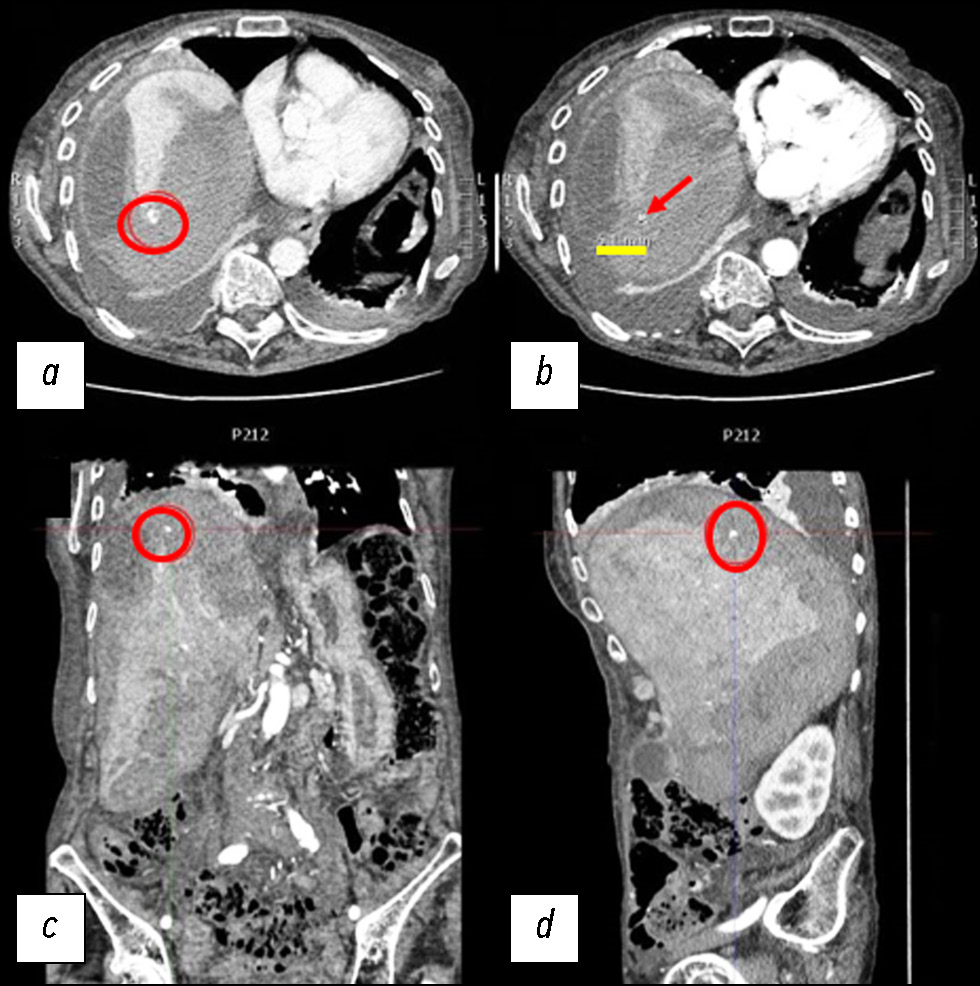

По данным УЗИ, паренхима печени была относительно неоднородной, с гипоэхогенными участками, некоторые из которых имели овальную форму. Учитывая эти данные, потребовалась КТ. Первую КТ выполняли без контрастирования, согласно требованиям отделения неотложной помощи. Кроме того, у пациентки были очень высокие показатели креатинина, что объяснялось её возрастом. По результатам первой КТ выявили несколько гиподенсных овальных участков в печени со специфическим ослаблением сигнала от жидкости (рис. 1).

Рис. 1. Снимки компьютерной томографии без контрастного усиления: a — аксиальная плоскость; b — корональная плоскость; c — сагиттальная плоскость.

На снимках в аксиальной плоскости сверху (справа, с указанием размеров), в корональной и сагиттальной плоскостях наблюдались неоднородное ослабление сигнала и увеличение печени с гиподенсными овальными образованиями и жидкостью повышенной плотности (25–30 единиц по шкале Хаунсфилда) в субкапсулярной области, самое большое из которых соответствовало VII сегменту печени и имело передне-заднюю ширину 8 см и максимальную толщину 35 мм. В брюшной полости наблюдался сопутствующий выпот.